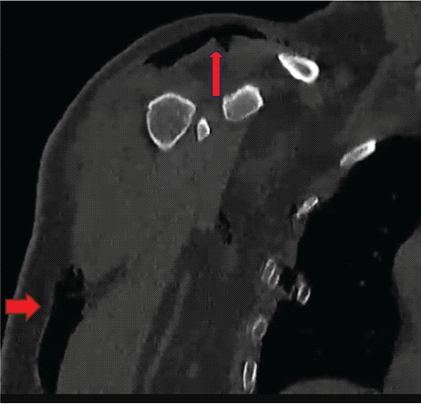

To evaluate the full extent of soft tissue air and rule out deeper involvement, a contrast-enhanced computed tomography (CT) scan of the thorax and shoulder was performed. It confirmed the presence of SE confined to the soft tissues of the axilla and upper arm (Fig. 3). There was no extension into the pleural cavity, no pneumomediastinum, and no vascular or pulmonary parenchymal injuries. The scapular body fracture was confirmed to be minimally displaced and extra-articular.

Figure 3: Coronal computed tomography image of the chest and left upper extremity. The red arrows highlight extensive subcutaneous air in the soft tissue planes of the upper limb (horizontal arrow) and axillary region (vertical arrow), consistent with subcutaneous emphysema.